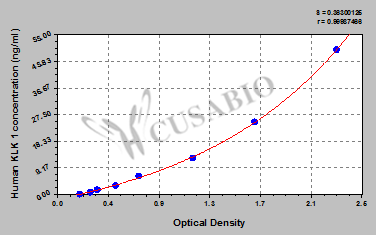

貨號:CSB-E11437h

規格:96T/48T

靈敏度:0.195 ng/mL

檢測范圍:0.78 ng/mL-50 ng/mL

These standard curves are provided for demonstration only. A standard curve should be generated for each set of samples assayed.